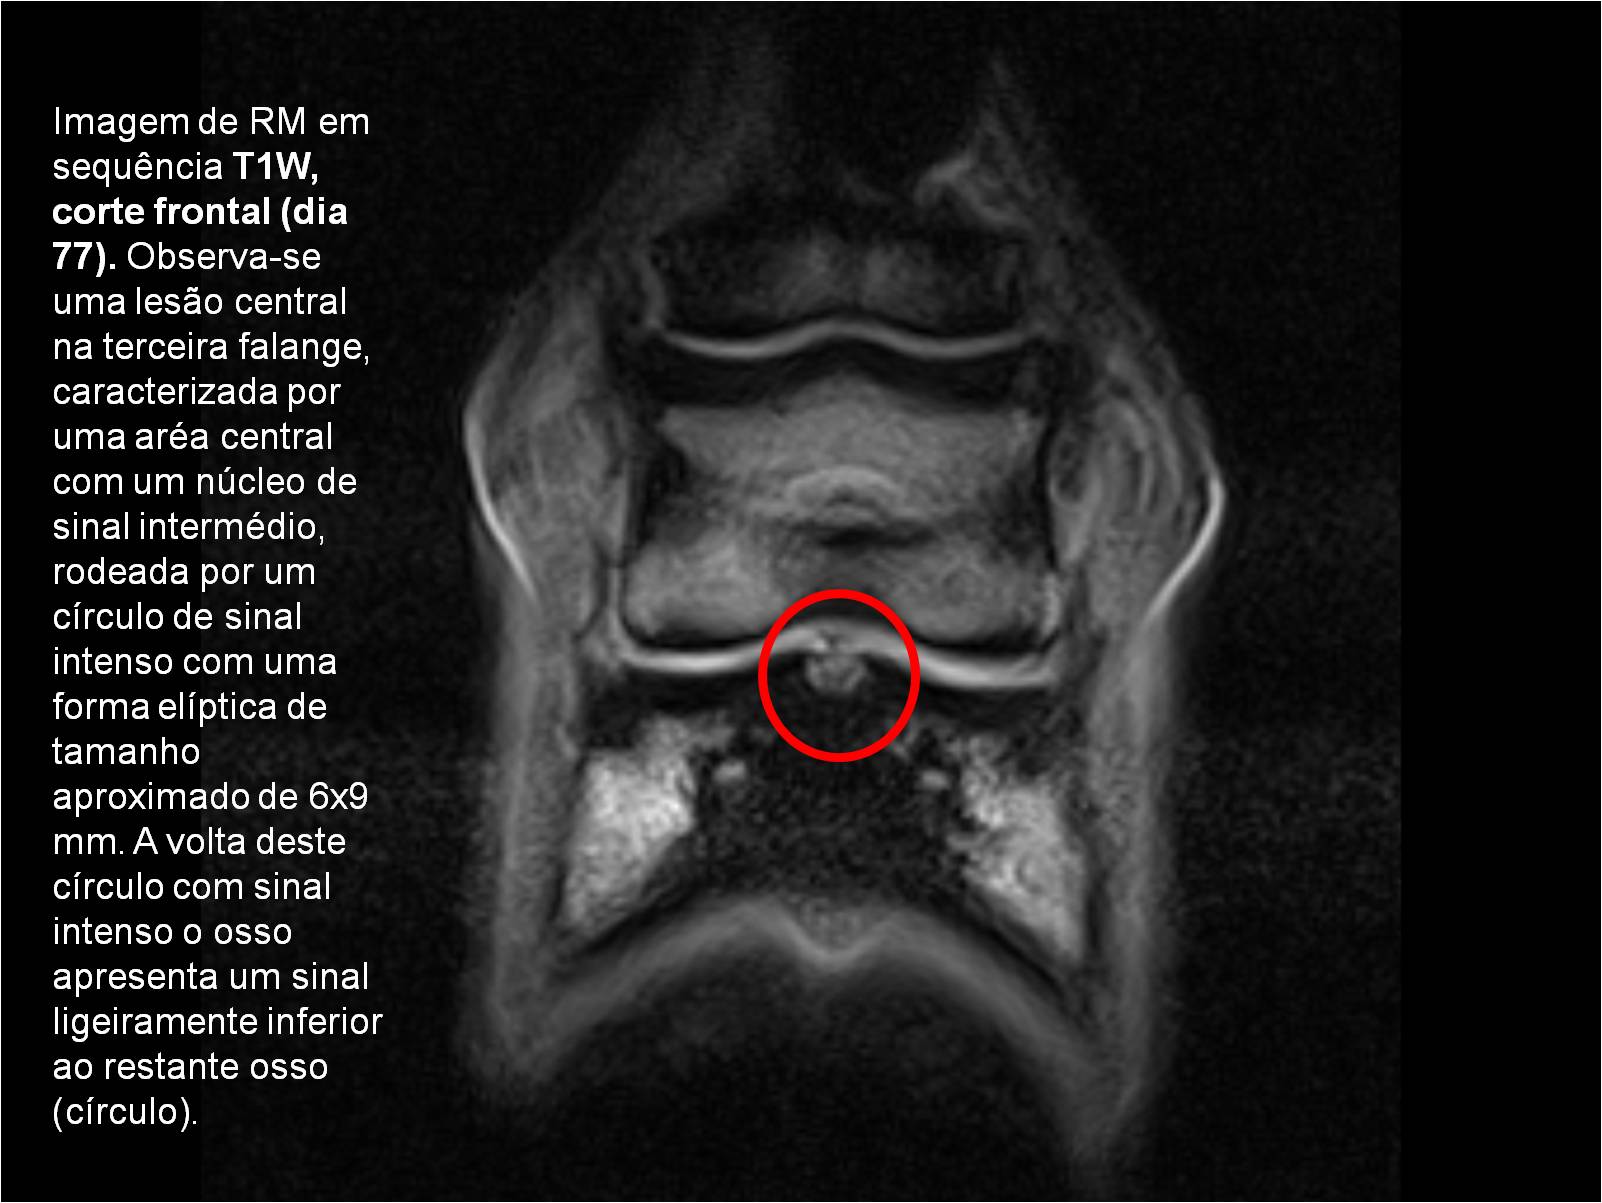

Publisher: Universidade de Évora

Abstract: O relatório de estágio encontra-se estruturado em três partes distintas. A primeira parte faz a caracterização das infraestruturas e funcionamento do Hospital Veterinário de Equinos de Lüsche, Oldenburg, Alemanha, assim como a análise casuística dos casos clínicos acompanhados durante os 6 meses de estágio. A segunda parte consiste de uma revisão bibliográfica sobre quistos do osso subcondral em equinos. Por fim, a terceira parte consta da apresentação e discussão de um caso clínico, nomeadamente o diagnóstico e acompanhamento imagiológico, por ressonância magnética, de um quisto subcondral na terceira falange num cavalo adulto; ### Abstract Equine Practice- Subcondral bone cyst of the third phalanx This internship report is divided in three parts. The first part characterizes the infrastructure and function of the Equine Hospital Lüsche, Oldenburg, Germany, as well as the casuistic of the clinical cases accompanied during the 6 month internship. The second part consists in a bibliographic review of cystic lesions of the subchondral bone in equines. The third part consists in a case report, the diagnostic and imagiological accompaniment, by use of magnetic resonance imaging, of a subchondral bone cyst in the distal phalanx of an adult equine.